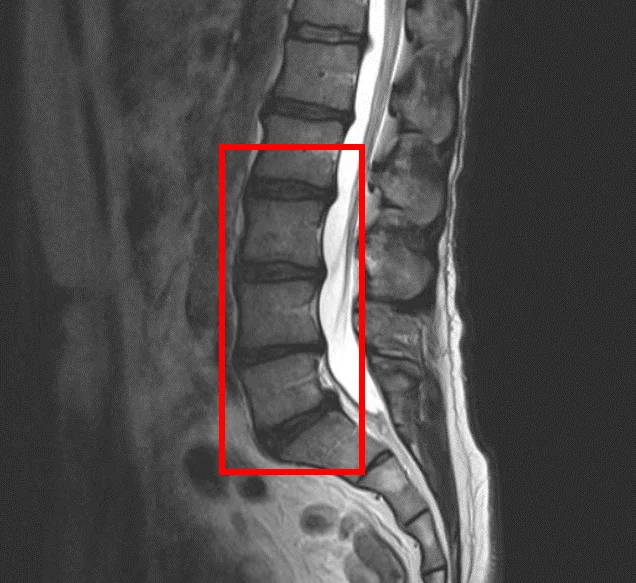

По данным МРТ и результатам осмотра пациента выявлена дегенерация межпозвоночных дисков L2/L3, L3/L4, L4/L5, L5/S1 и стеноз межпозвонковых отверстий.

В клинике проведена селлгель-терапия на 4 межпозвоночных дисках (L2/L3, L3/L4, L4/L5, L5/S1).